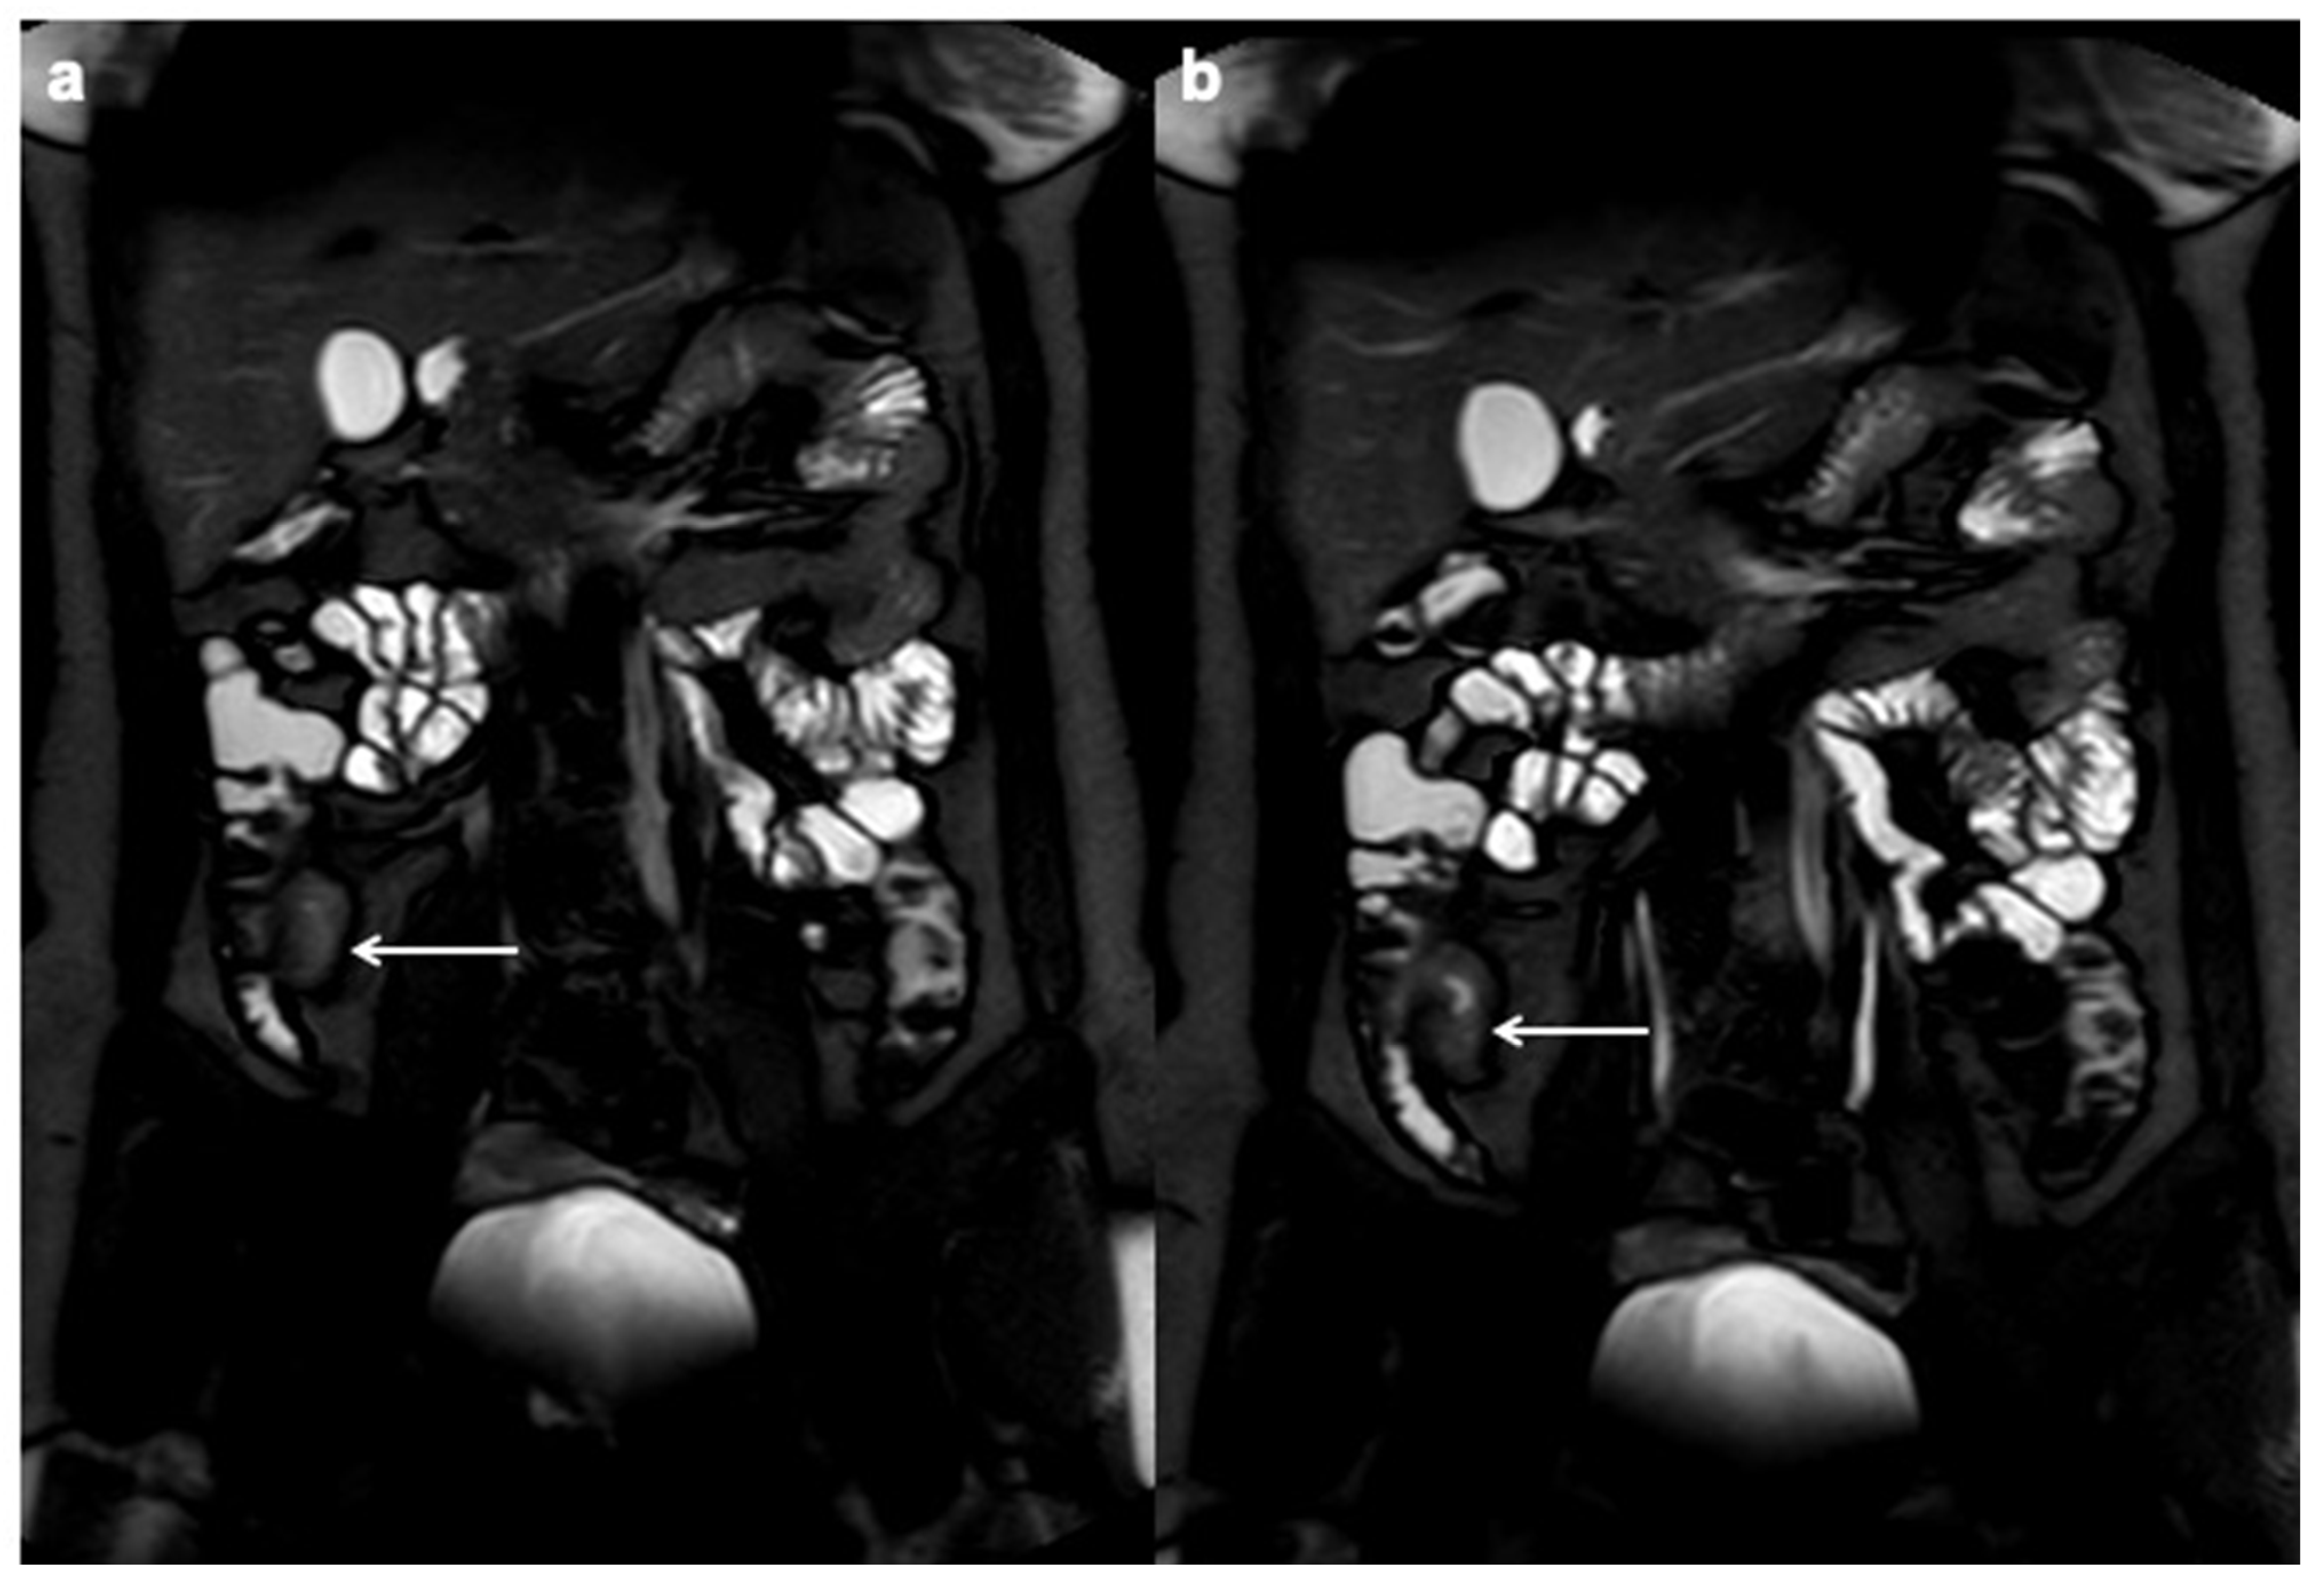

10. Imaging Findings Associated with Active CD Inflammation

- Church, P.C.; Turner, D.; Feldman, B.M.; Walters, T.D.; Greer, M.-L.; Amitai, M.M.; Griffiths, A.M.; the ImageKids study group. Systematic review with meta-analysis: Magnetic resonance enterography signs for the detection of inflammation and intestinal damage in Crohn’s disease. Aliment. Pharmacol. Ther. 2014, 41, 153–166. [Google Scholar] [CrossRef]

- Tolan, D.J.M.; Greenhalgh, R.; Zealley, I.A.; Halligan, S.; Taylor, S.A. MR Enterographic Manifestations of Small Bowel Crohn Disease. RadioGraphics 2010, 30, 367–384. [Google Scholar] [CrossRef] [Green Version]

- Sinha, R.; Verma, R.; Verma, S.; Rajesh, A. MR Enterography of Crohn Disease: Part 2, Imaging and Pathologic Findings. Am. J. Roentgenol. 2011, 197, 80–85. [Google Scholar] [CrossRef] [Green Version]

- Seo, N.; Park, S.H.; Kim, K.-J.; Kang, B.-K.; Lee, Y.; Yang, S.-K.; Ye, B.D.; Park, S.H.; Kim, S.Y.; Baek, S.; et al. MR Enterography for the Evaluation of Small-Bowel Inflammation in Crohn Disease by Using Diffusion-weighted Imaging without Intravenous Contrast Material: A Prospective Noninferiority Study. Radiology 2016, 278, 762–772. [Google Scholar] [CrossRef]

- Park, S.H. DWI at MR Enterography for Evaluating Bowel Inflammation in Crohn Disease. Am. J. Roentgenol. 2016, 207, 40–48. [Google Scholar] [CrossRef]

- Kiryu, S.; Dodanuki, K.; Takao, H.; Watanabe, M.; Inoue, Y.; Takazoe, M.; Sahara, R.; Unuma, K.; Ohtomo, K. Free-breathing diffusion-weighted imaging for the assessment of inflammatory activity in Crohn’s disease. J. Magn. Reson. Imaging 2009, 29, 880–886. [Google Scholar] [CrossRef] [PubMed]